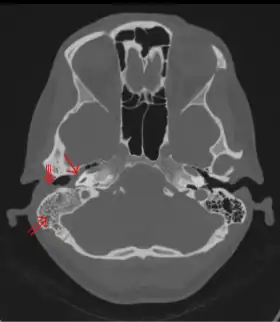

Un examen de la cabeza puede revelar signos de mastoiditis. Los siguientes exámenes pueden mostrar una anomalía en el hueso mastoideo:

- Tomografía computarizada del oído

- Tomografía computarizada de la cabeza